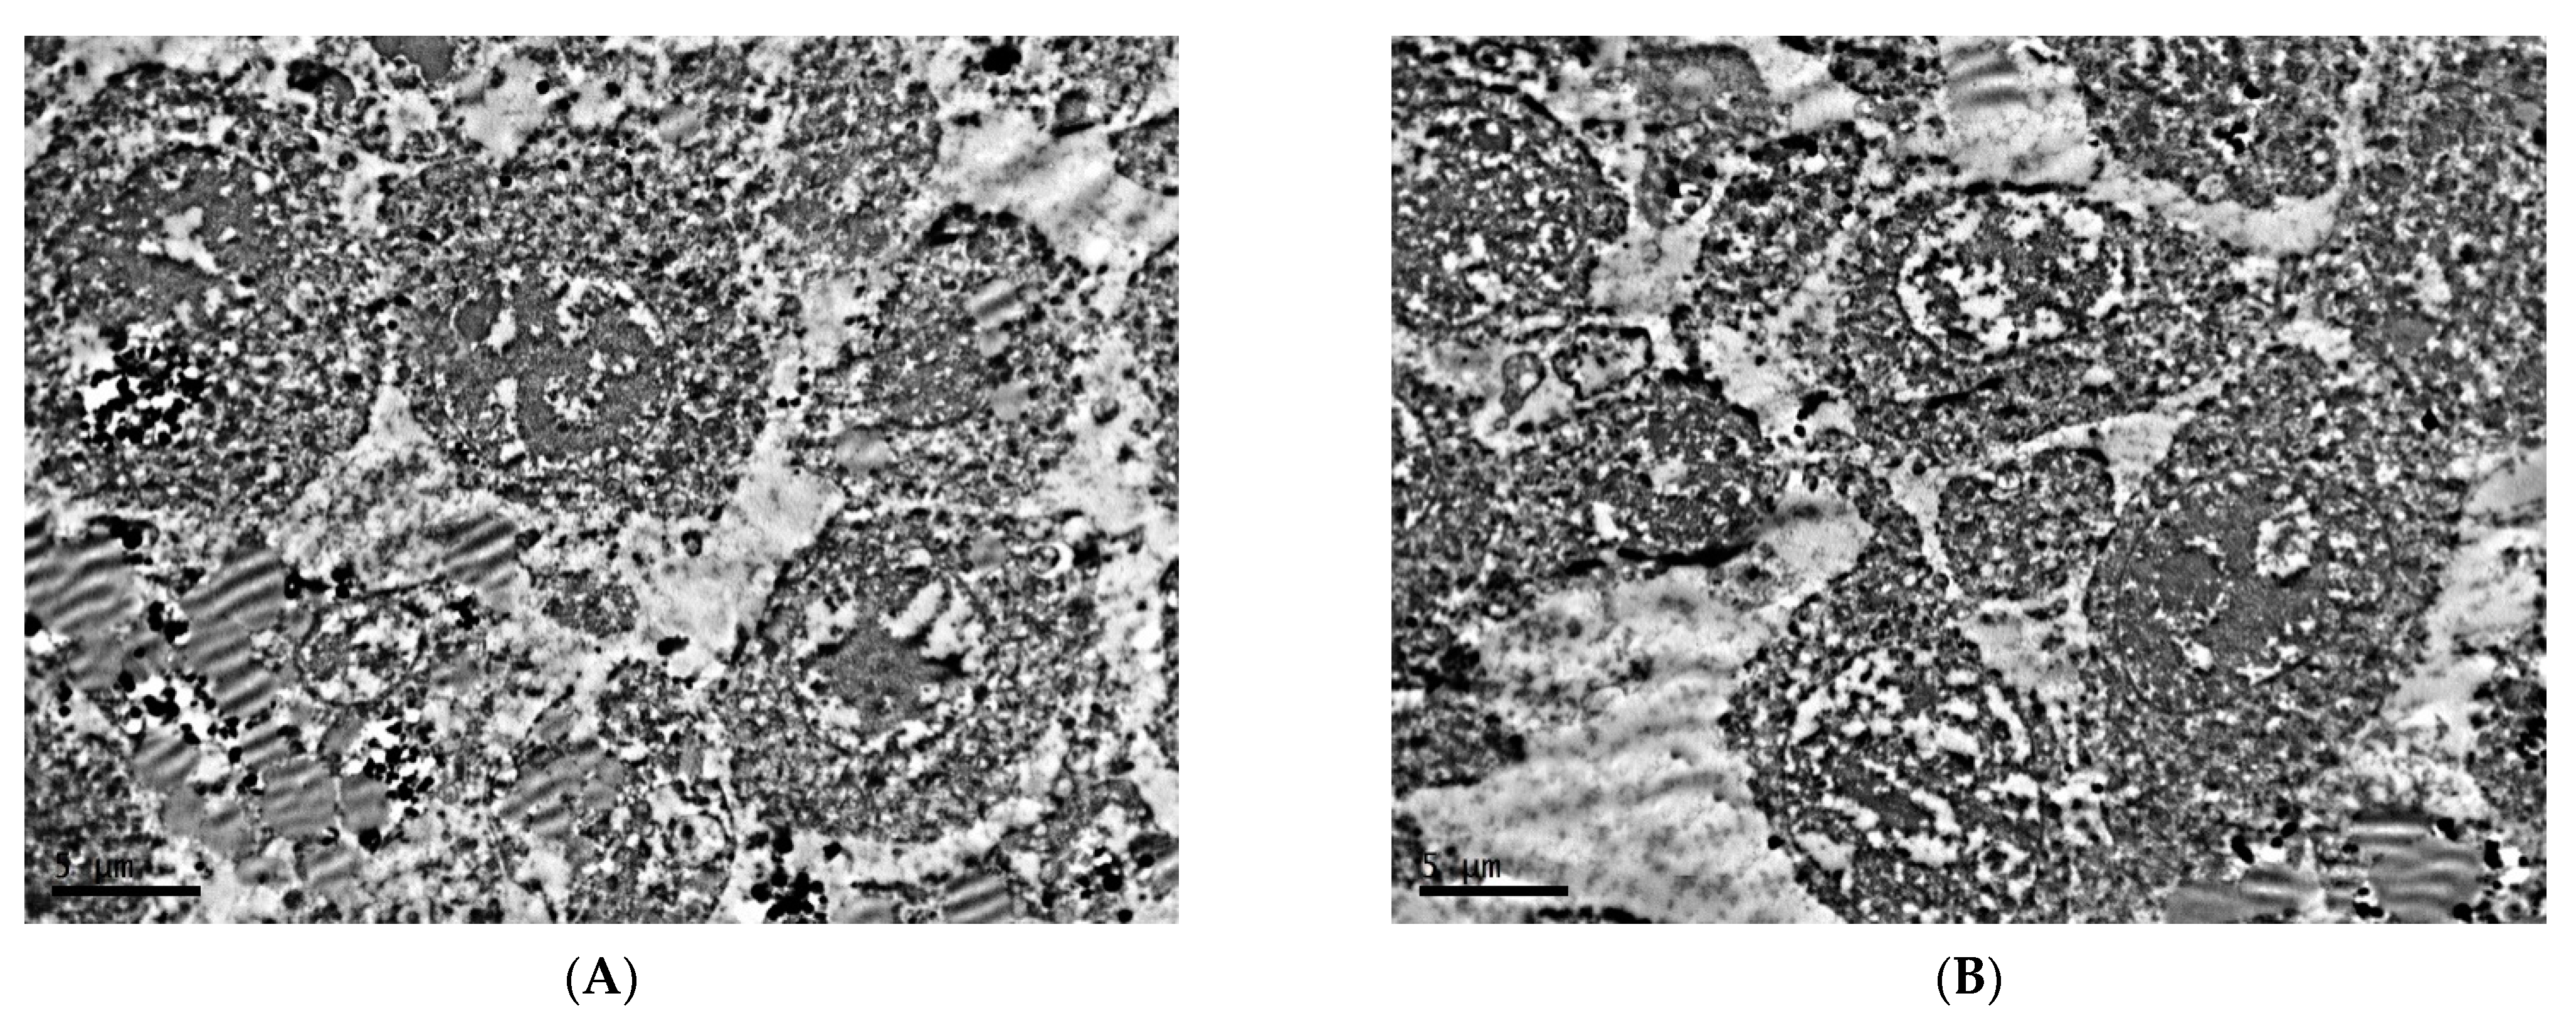

2.1. Ultrastructure of Transplantable Malignant Melanoma B16 in Conditions of Fixed Light Regime

2.2. Ultrastructure of Transplantable Malignant Melanoma B16 in Conditions of Constant Lighting Regime